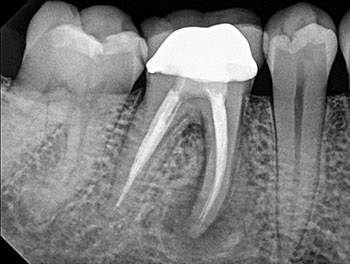

Case 10: Failing ‘well done’ NSRCT

This patient’s teeth #30 and #31 were treated by an endodontist. The endodontist found all the canals, achieved patency and shaped and filled each canal to length. When the periradicular tissues surrounding both teeth failed to heal, the endodontist recommended extracting both teeth because of VRFs. By then, tooth #31 developed a J-shaped lesion, suggestive of a VRF. Nothing suggested that tooth #30 had a VRF, other than that it was a “good-looking” or “well-done” NSRCT that failed. Yet both were recommended for extraction.

The somewhat skeptical patient came to see if these teeth really needed to be extracted. Nonsurgical retreatment was recommended. The patient didn’t want to lose his teeth, but he also didn’t want to pay to re-treat teeth that could not be saved.

Tooth #31—the tooth that was more likely to be fractured—was addressed first. To maximize the likelihood of healing, this tooth was treated in multiple visits using a calcium hydroxide intracanal medicament and obturated after bony healing was complete. The patient was delighted that his tooth had been saved, but also somewhat perplexed that the original endodontist gave up on a tooth that could have been saved. He has now scheduled re-treatment for tooth #30.

More than a few cases have been seen for second opinions after a dentist completed RCT on a tooth that failed shortly after, then told the patient to extract the tooth because it must be cracked because the NSRCT “looked perfect” radiographically. Although shaping and obturation can be judged radiographically, the most important factor—disinfection—cannot.

Fig.40: Postop PA.